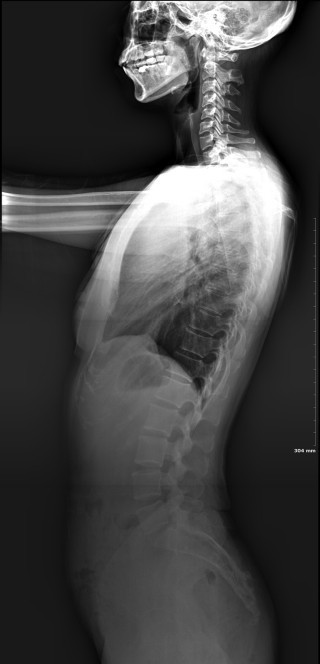

2019년 9월 촬영

<사진의 맨 오름쪽>

발레를 배우며 구부정한 자세라는 것을 알게 되어 신경쓴다고 했는데도 저 정도입니다. 학부모 모임에서 저런 모습으로 찍혀 너무 충격적이었습니다.

사례발표 시 snpe 시작 후라고 말했는데, 시기에 대한 착각이 있어서 바로잡습니다.